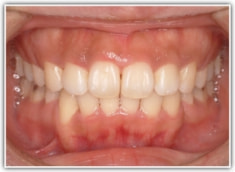

上顎前突ケース

治療法:表の矯正(T21ブラケット)

治療前